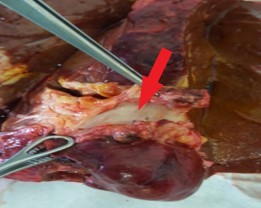

Материалы и методы. С 2017-го по 2021 г. в ФГБУ «РНЦРХТ им. академика А.М. Гранова» в протокол лечения нерезектабельной опухоли Клацкина с последующей трансплантацией печени было включено 6 пациентов. Неоадъювантное лечение включало эндобилиарную фотодинамическую терапию, регионарную и системную химиотерапию. Каждый метод применялся минимум трижды в течение четырех-пяти месяцев с радиологической оценкой и определением уровня Са19-9. Пациенты вносились в лист ожидания при снижении онкомаркера, отсутствии радиологических признаков прогрессии заболевания и без острого холангита. Реципиентам выполнялась лапароскопическая ревизия брюшной полости на предмет канцероматоза и оценка лимфоузлов печеночнодвенадцатиперстной связки со срочным морфологическим исследованием. При отсутствии внепеченочного распространения производилась трансплантация печени по классической методике с паракавальной, парааортальной и гепатодуоденальной лимфодиссекцией, билиодигестивным анастомозом на отключенной по Ру петле тонкой кишки. Операция выполнена трем пациентам, все из них – мужчины. Возраст колебался от 40 до 55 лет (средний – 48). Среднее время от начала лечения до трансплантации составило 9,3 месяца (от 6 до 14). Средний уровень Са19-9 на момент выполнения вмешательства составил 81,3 МЕ/мл (от 8 до 212).

Результаты. У трех пациентов, несмотря на лечение, отмечен рост уровня Са19-9 более чем в два раза в среднем за четыре месяца. У двух из них выявлена прогрессия заболевания согласно данным компьютерной томографии по RECIST. У одного пациента выявлен канцероматоз при диагностической лапароскопии. У трех пациентов Са19-9 снизился более чем в четыре раза. У двух из этих пациентов радиологически подтверждена стабилизация заболевания, у одного – частичный ответ. Один пациент умер через три года после трансплантации от сепсиса в исходе вторичного билиарного цирроза и билиарных абсцессов без признаков прогрессирования. Два пациента живы по настоящее время на протяжении 6 и 21 месяцев без признаков прогрессирования опухоли.